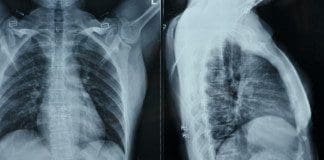

Have you been experiencing pain shooting from your lower back to your feet? Does it hurt when you are doing daily activities like walking or running? Have you been experiencing muscle stiffness in your lower back or your neck? You might be suffering from a disc herniation from wear and tear from your spine. Research studies have defined that herniation on the spine happens when the spinal discs between the spinal joint columns are damaged. Natural wear and tear on the spine when the muscles have been overworked due to heavy lifting or when the outer layer of the spinal discs starts to crack under pressure, letting the inner layers protrude out of alignment of the spine and press on the nerve roots that are connected to the spine.

Additional information has provided that disc herniation is usually associated with DDD or disc degeneration disease and contributes to low back pain. When a herniated disc starts to affect the spinal column and press on the spinal nerve roots extending all over to work with the back muscles providing motor and sensory function for the body to move, it increases the inflammatory pathways to cause radiating pain to the body. Wear and tear herniation also causes the inner walls of the spinal disc to become weak due to dehydration when the outer layer is cracked. Research studies have also mentioned that the cervical and lumbar regions of the spine are susceptible to disc herniation due to spinal pathologies that affect the spine itself. Spinal pathologies can include RA (rheumatoid arthritis), fractures, osteoporosis, and infections associated with herniated discs that can cause significant issues on the back and make a person in more pain than they already are.

Disc herniation is associated with low back pain, but other spinal issues that cause disc herniation will affect the back even more, when it is not treated. When disc herniation starts to affect the spine, it affects the back, especially the lower back. Research studies have shown the spinal disc in the spine begins to protrude out, inflammation and nerve compression begin to affect the lower back, causing lumbar radicular pain. Other research studies have shown that lumbar disc herniation causes changes in disc height in the spine while shrinking the dural sac. This causes the spinal joints to rub against each other. At the same time, the herniated disc protrudes to compress the spinal nerve roots, thus sending sudden, throbbing pain all over the back, making the individual miserable.